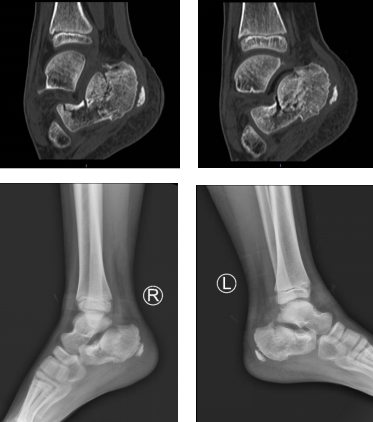

术前片

魏医生给孩子做了仔细检查,患者俩脚跟明显红肿,拍片显示双侧跟骨骨折,断端错位,累及周围关节。考虑到孩子年龄幼小,为了以最小的创伤完成治疗,以最快的速度康复,足踝二病区徐明亮主任和手术小组讨论后决定给孩子施行踝关节镜下微创骨折复位手术。

术后